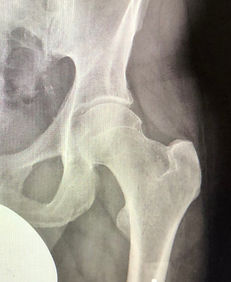

I am a Fellowship-trained Consultant Orthopaedic Surgeon with a specialist practice in hip and knee disorders. I offer a scope of services to patients when their native joint can be saved, or requires replacement in more advanced cases with established arthritis. My sub-speciality interest lies in hip joint preservation. I am an expert in and offer surgery for hip impingement, and bone and soft tissue disorders around the hip. This surgery aims to resolve the symptoms and prevent or delay the onset of hip arthritis by addressing underlying problems. I strive to provide superior evidence-based care to return the patients to their optimal function.